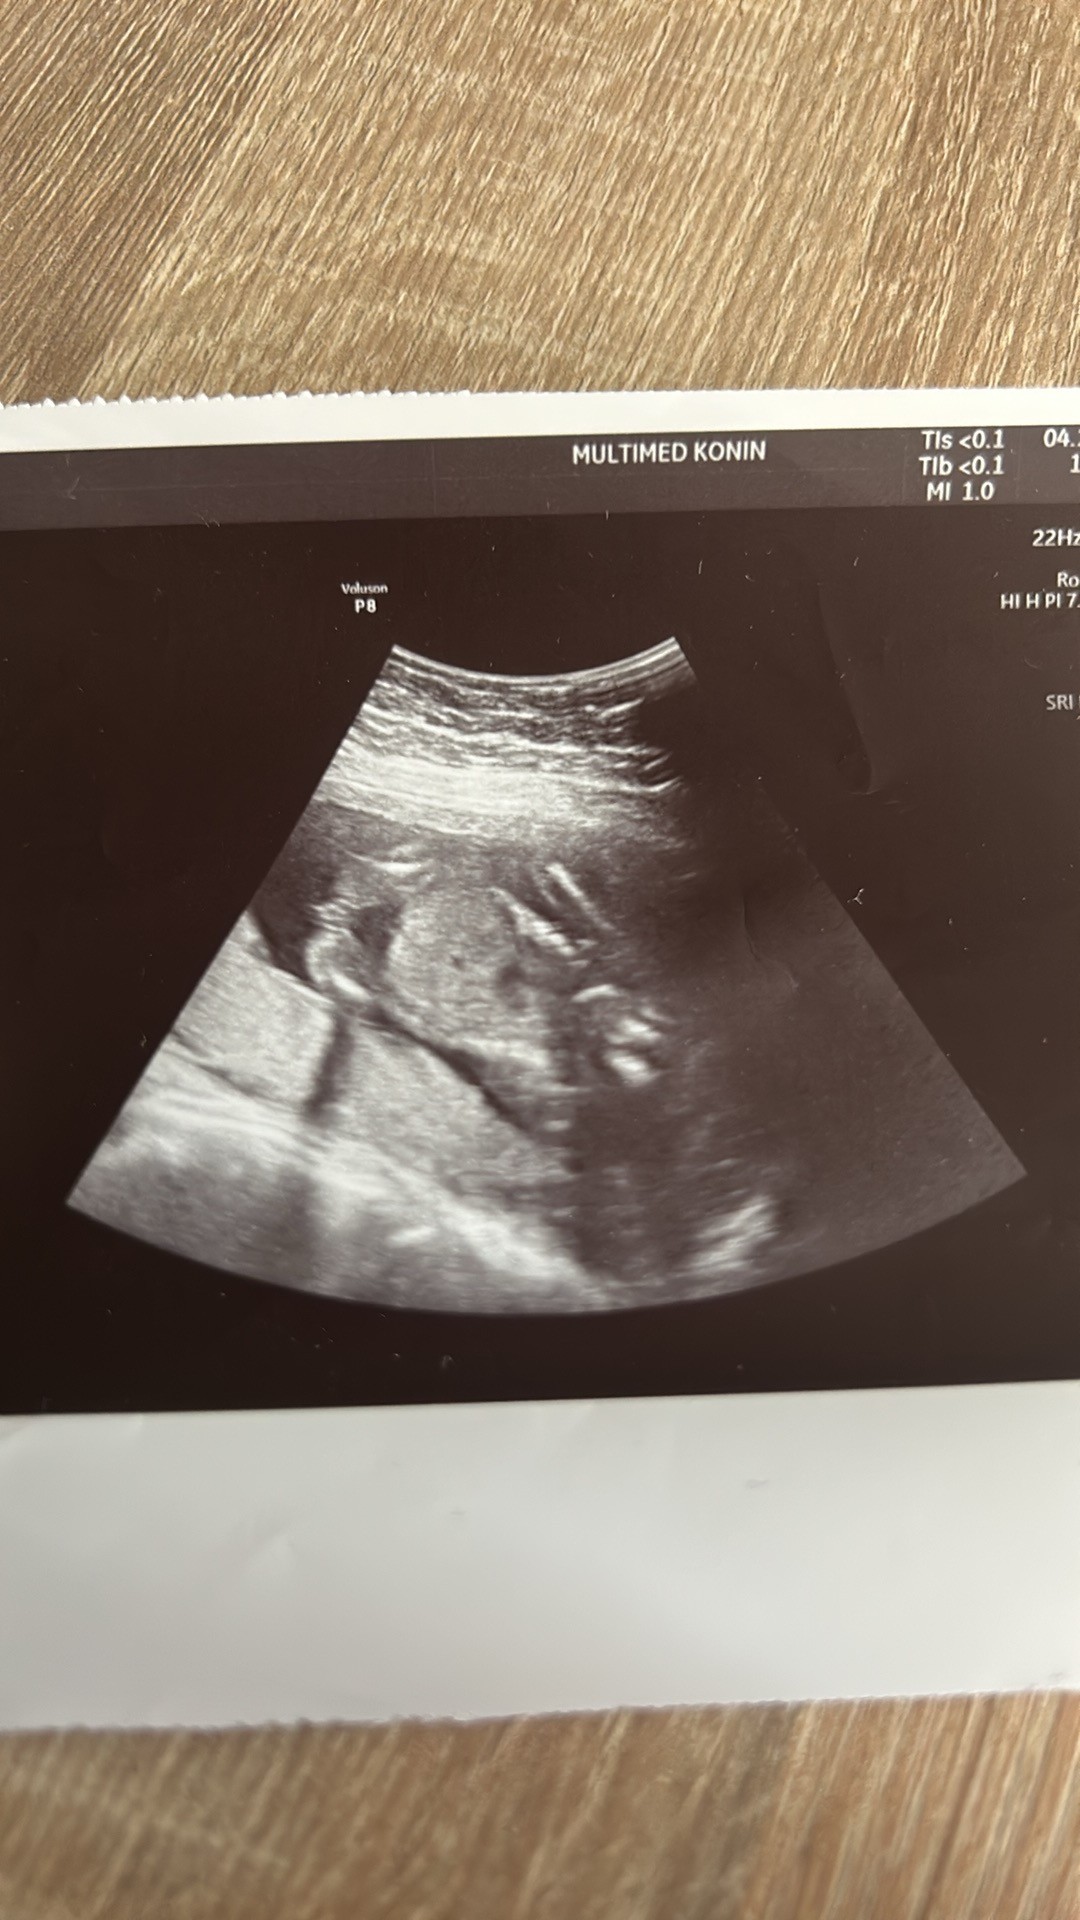

Jaka może być płeć

Cześć. Mój ginekolog który prowadzi ciążę powiedział mi że będzie chłopiec ale teraz na badaniu prenatalnym ginekolog powiedział że dziewczynka. Jak myślicie dziewczyny chłopiec czy dziewczynka?